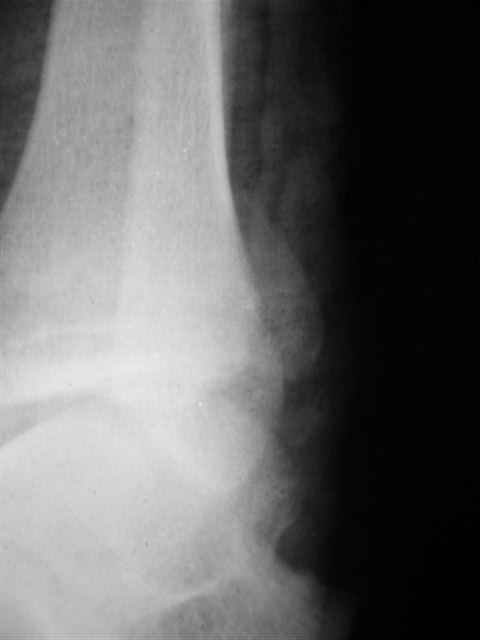

> Если Вас не затруднит, пришлите, пожалуйста, рентгенограммы. Я

> интересуюсь тактикой лечения повреждений голеностопного сустава.

> Хочется посмотреть, как лечат коллеги.

Ничего сверхъестественного, но если есть интерес, то в понедельник пересниму Рг-граммы и отправлю.

Уважаемый Иван,

Я предупреждал, что ничего сверхъестественного. Каюсь, что одна из спиц прошла несколько дальше, чем нужно было, но главное - перелом стабилизирован и больной работает суставом в полном объёме, несмотря на представленную раннее травму коленного сустава.